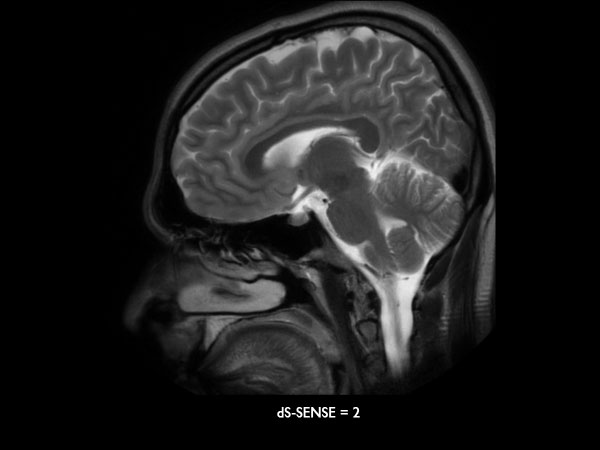

Sagittal T2w MultiVane XD